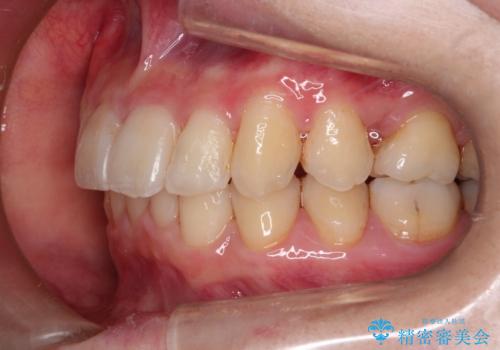

- 前歯の見た目の改善を希望され来院された患者様です。

初診時の歯並びの状態としては、上下ともに前歯部の中等度のがたつきがあり、下の前歯は本来生えるはずの歯が2本生まれつき欠損している状態でした。

抜歯ありワイヤー矯正にて治療を行い、抜歯する歯に関しては虫歯で抜歯が必要な部分を有効活用することで、健康な歯を保存するように努めました。

噛み合わせが深い過蓋咬合という状態でもあったため、下の歯の装置をつけたり、嚙み合わせを上げる(下の歯が見える状態にする)ことにたいへんに苦労した症例でした。

見た目、嚙み合わせ及び、治療期間や施術内容に大変ご満足いただきました。